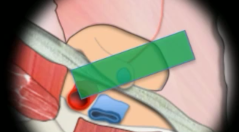

Filet

- Au niveau de l’orifice inguinal profond

- Trou pour laisser le cordon spermatique

- Masque tout en echo (bande hyperechogène et cône d’ombre)